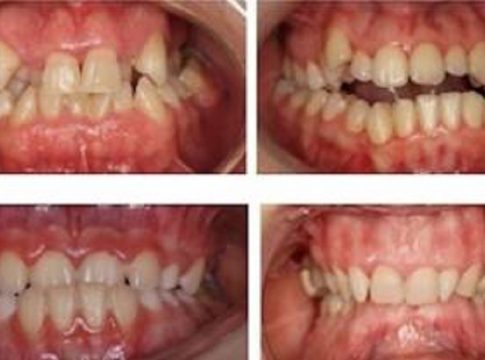

En la búsqueda de ese equilibrio perfecto, la doctora Lucia Rodríguez Fonseca, ortodoncista del Hospital La Luz de Madrid, afirma que los principales problemas ortodóncicos a los que nos enfrentamos son las alteraciones de la erupción (donde destacarían la erupción ectópica, significa que el diente erupciona lejos de la posición normal y las impactaciones dentarias, es decir, los dientes no puede salir al quedar incluido en el hueso o encía), las anomalías volumétricas (apiñamiento o presencia de diastemas), maloclusiones de Clase II o Clase III, mordida abierta anterior y posterior, mordida profunda, así como maloclusiones transversales (mordida cruzada posterior unilateral, bilateral o mordida en tijera).

La resolución de estos problemas redundará en el bienestar del paciente, siendo numerosos los beneficios de un tratamiento ortodóncico. Para la doctora Rodríguez Fonseca, la corrección de maloclusiones y malposiciones dentarias, permite recuperar la funcionalidad de la boca mejorando la masticación, ingesta y digestión de alimentos. Disminuye el riesgo de desgaste dental y se mejora su higiene, reduciendo así el riesgo de caries o enfermedad periodontal, así como se perfecciona la estética, con repercusión en el bienestar psicosocial.